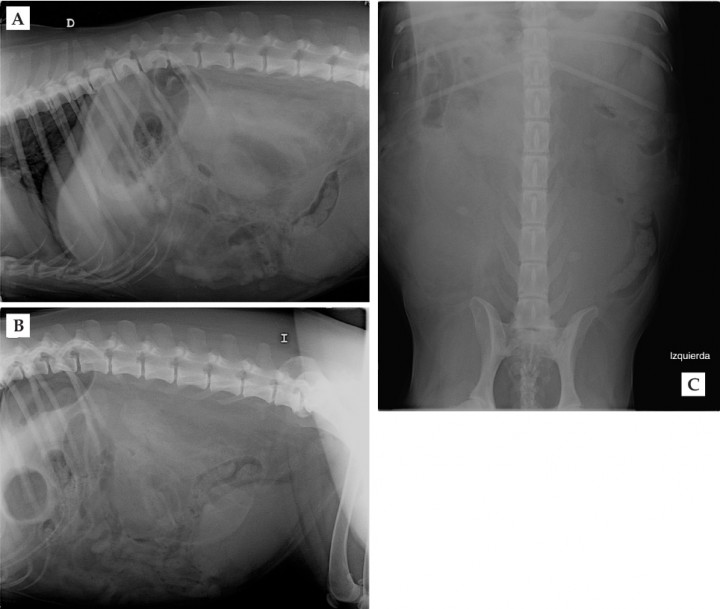

Historia clínica

<p>Radiografía de abdomen lateral derecha (A), lateral izquierda (B) y ventrodorsal (C).</p>

Radiografía de abdomen lateral derecha (A), lateral izquierda (B) y ventrodorsal (C).

Se observa una masa de opacidad tejido blando y bordes mal definidos localizada en la zona retroperitoneal derecha que desplaza el paquete intestinal y el riñón derecho ventral y caudalmente. En la proyección ventrodorsal también se visualiza una masa de opacidad tejido blando y bordes mal definidos que ocupa gran parte del abdomen derecho caudal. Existe pérdida de detalle en la zona retroperitoneal y peritoneal. El hígado aparece reducido de tamaño, causando un desplazamiento craneal del eje gástrico. Se visualiza espondilosis a nivel T8-T9, T10-T11, T12-T13 y L7-S1. El resto de estructuras abdominales aparecen dentro de límites normales (Fig. 2).